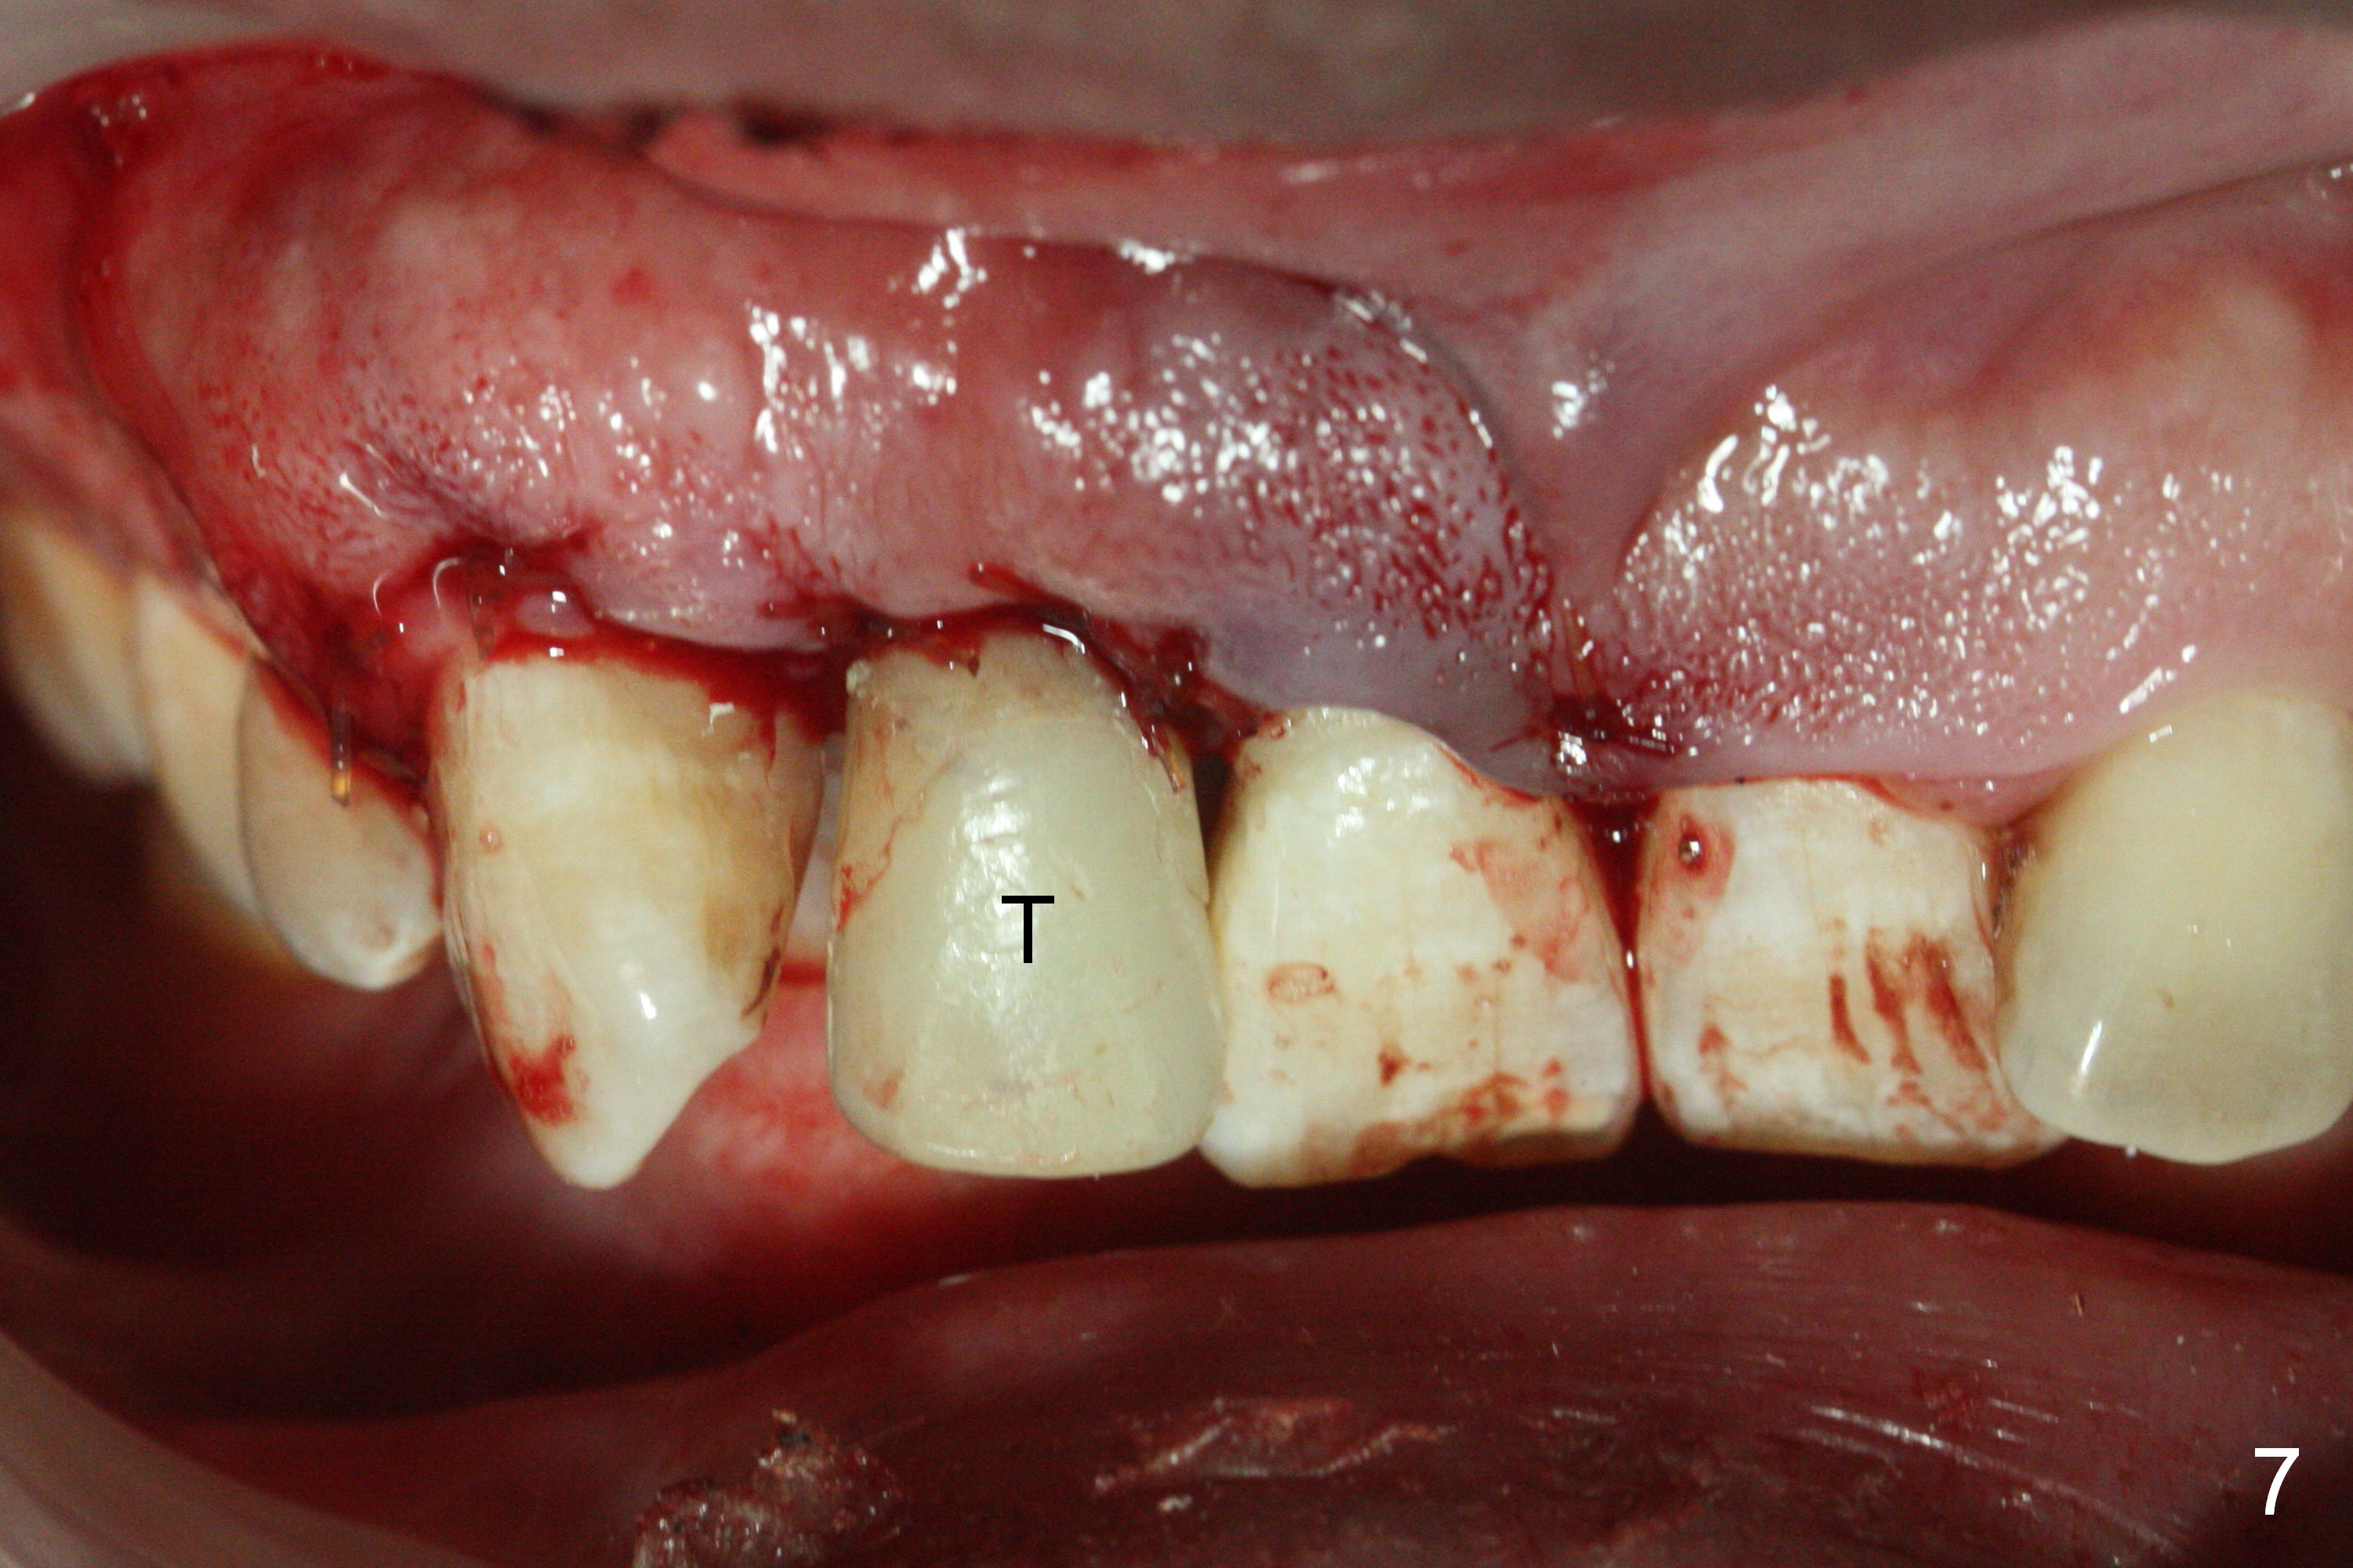

When the flaps are raised, the buccal plate is found to be perforated (Fig.2 *); osteotomy is being established in the narrow palatal wall (<). When a 3x17 mm (tissue-level) 15 ° 1-piece implant is placed (Fig.3,5 P), the incisal end of the implant is between the incisal edge of the central incisors and that of the tooth #10 (Fig.6) so that the temporary crown (Fig.7 T) is slightly buccal with sufficient palatal clearance with the opposing dentition.